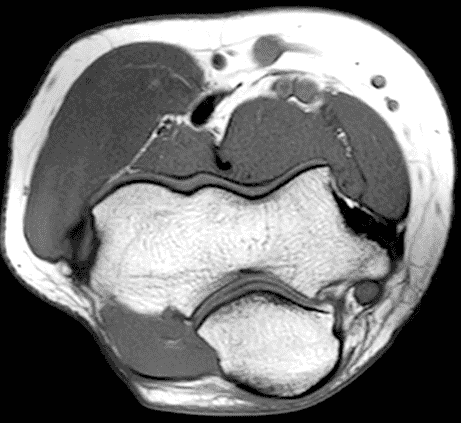

A 55-year-old man complains of pain, numbness, and tingling in the ulnar aspect of the hand and in the small and ring fingers. The symptoms are more severe with elbow flexion and during sleep. He has no muscle weakness or history of trauma. Axial T1-weighted (1A, 1B) and fat-suppressed, fluid-sensitive (1C, 1D) images are shown. What are the findings? What is your diagnosis?

Figure 2: At the level of the cubital tunnel (2A and 2C), identifiable by the thin cubital tunnel retinaculum (yellow arrow), the ulnar nerve (red arrow) is focally enlarged and hyperintense compared to the nerve more distally (2B and 2D), where it lies between the two heads of the flexor carpi ulnaris muscle (asterisks). No soft tissue mass is present.